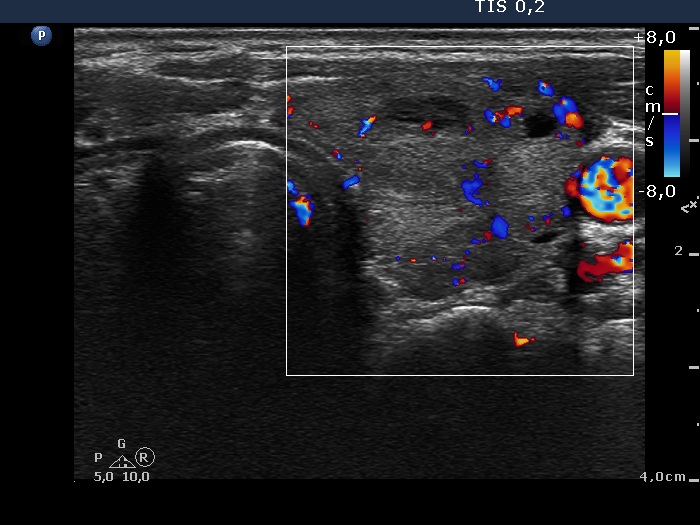

Consecutively operated patients with autoimmune thyroid disease - case 18 (1741) (ultrasonographic picture 8)

Left lobe, longitudinal scan, color Doppler mode. The vascularization is average.